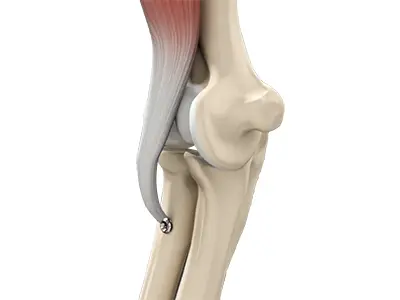

Distal Biceps Repair

The biceps is a large muscle located in the front of your upper arm and runs from the shoulder to the elbow joint.

Biceps Tendon Repair

Biceps tendon repair is a surgical procedure to restore a biceps tendon that has been torn or ruptured by severe trauma or injury.